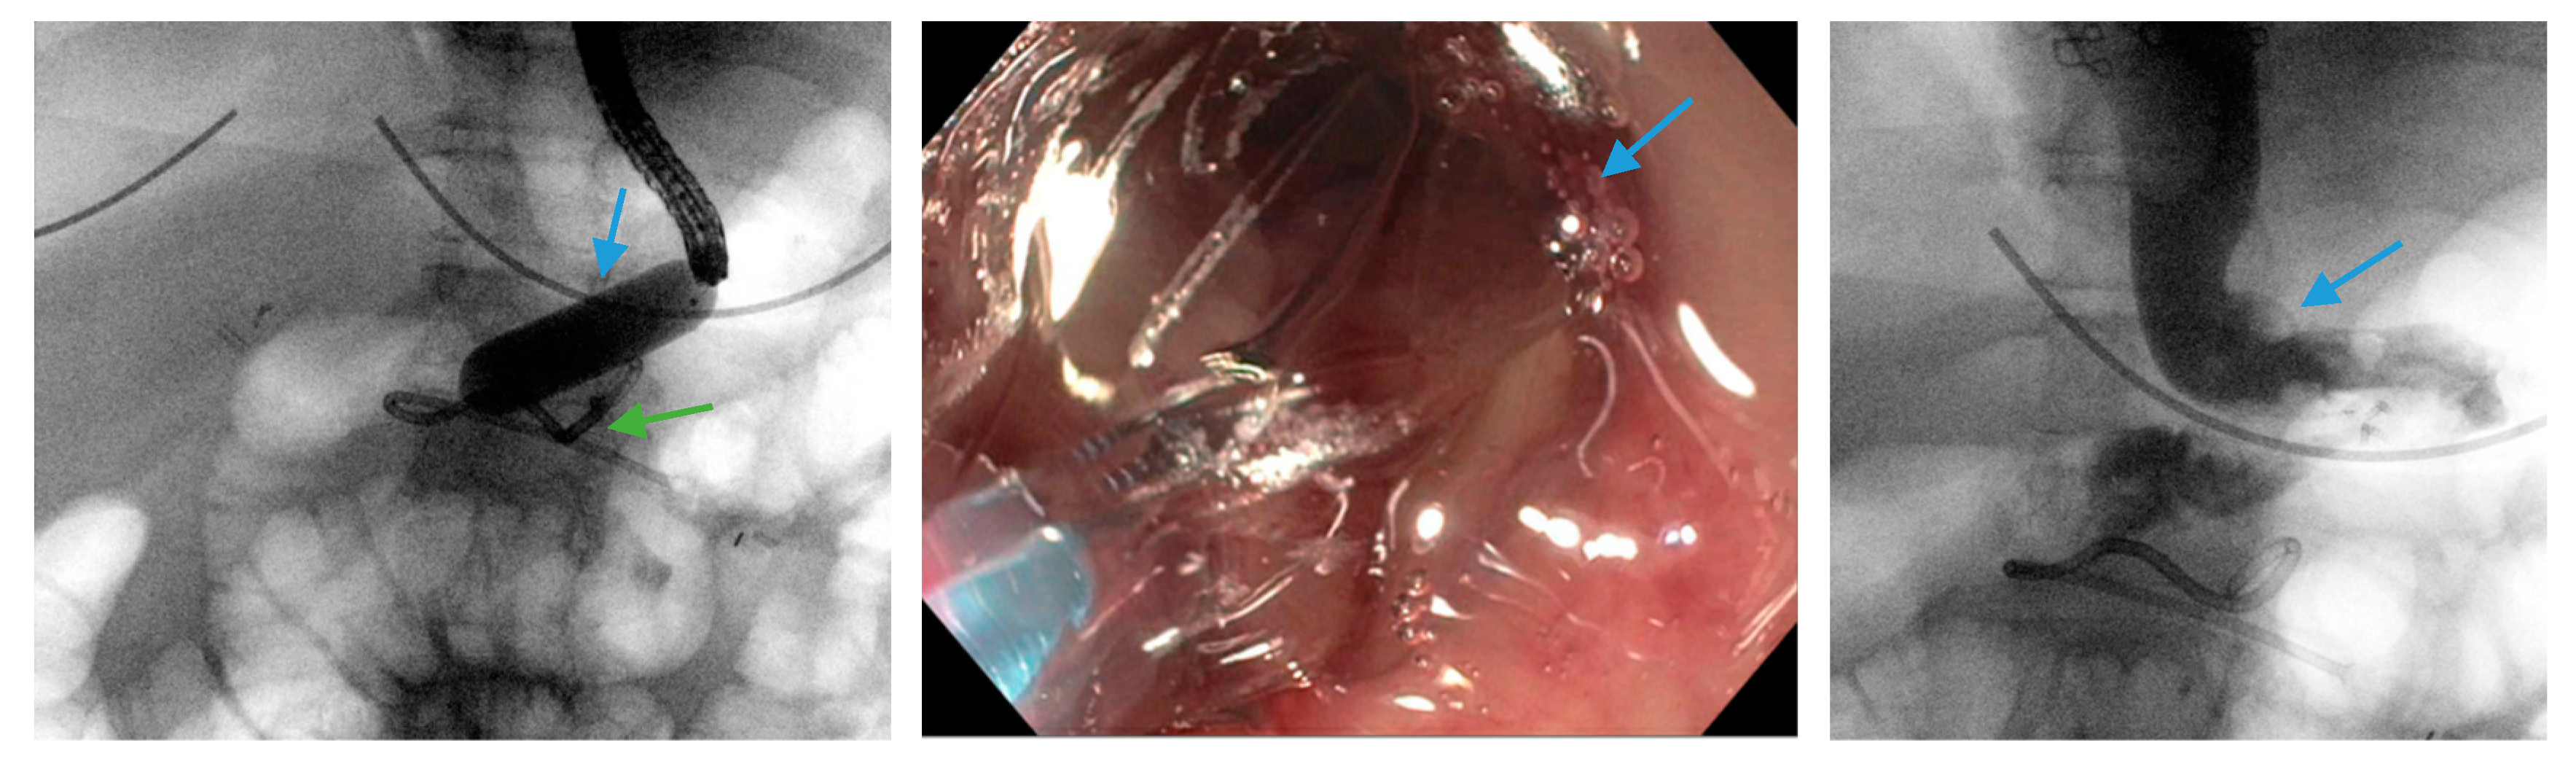

3.3. Endoscopic Internal Drainage with Transgastric Double-Pigtail Stents

3.4. Over-the-Scope Clips